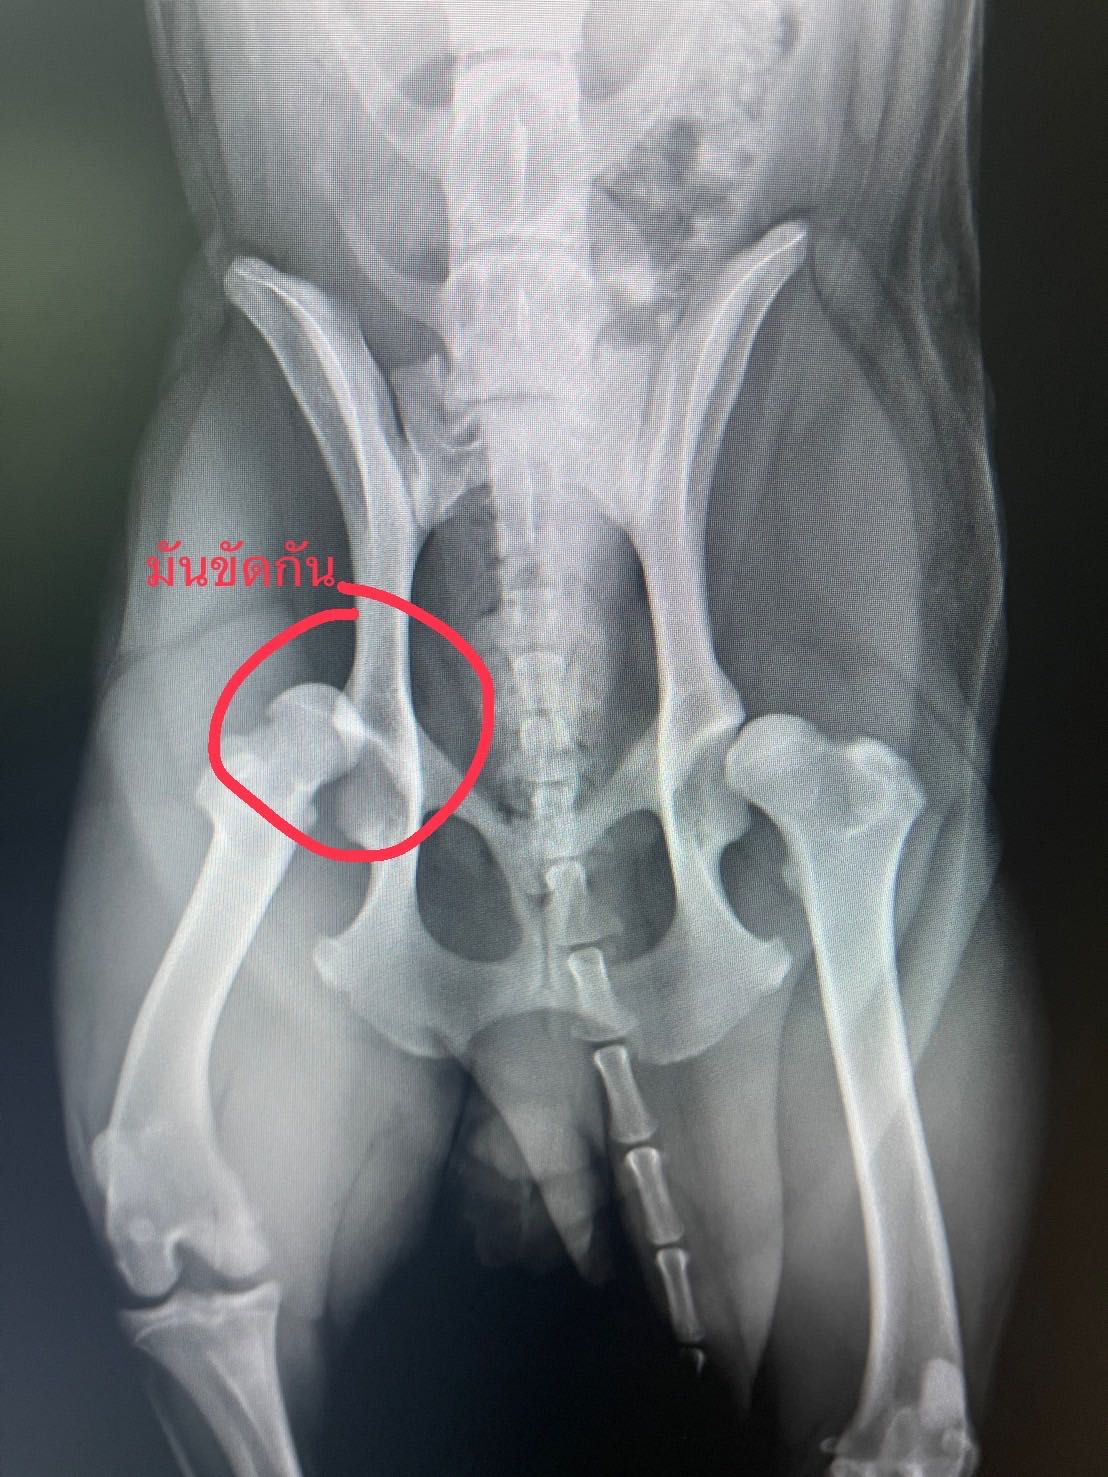

วันศุกร์ที่ 28 ที่ผ่านมาน้องหมาเรากระโดดขึ้นเตียงเพราะวิ่งเล่น แต่ก้าวไม่พ้นขอบเตียง ร่วงจากเตียงจนช่วงสะโพกกระแทกพื้น สะโพกหลุด แต่ไม่มีกระดูกร้าวหรือแตกนะคะ

ในวันแรก รีบพาไป รพ.สัตว์ใกล้บ้าน หมอตรวจเบื้องต้น ได้ฟิล์ม x-ray มา